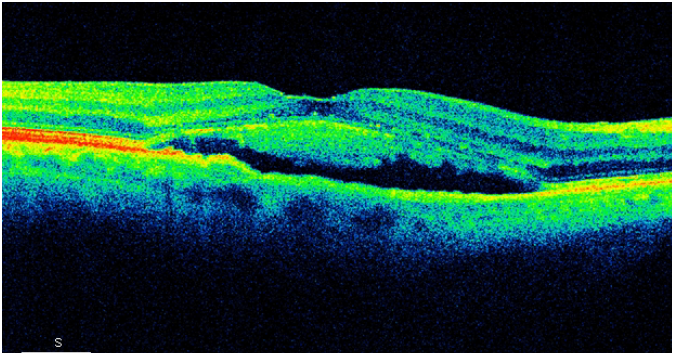

Centralna surowicza chorioretinopatia (CSCR) – aktualny stan wiedzy i opcje terapeutyczne